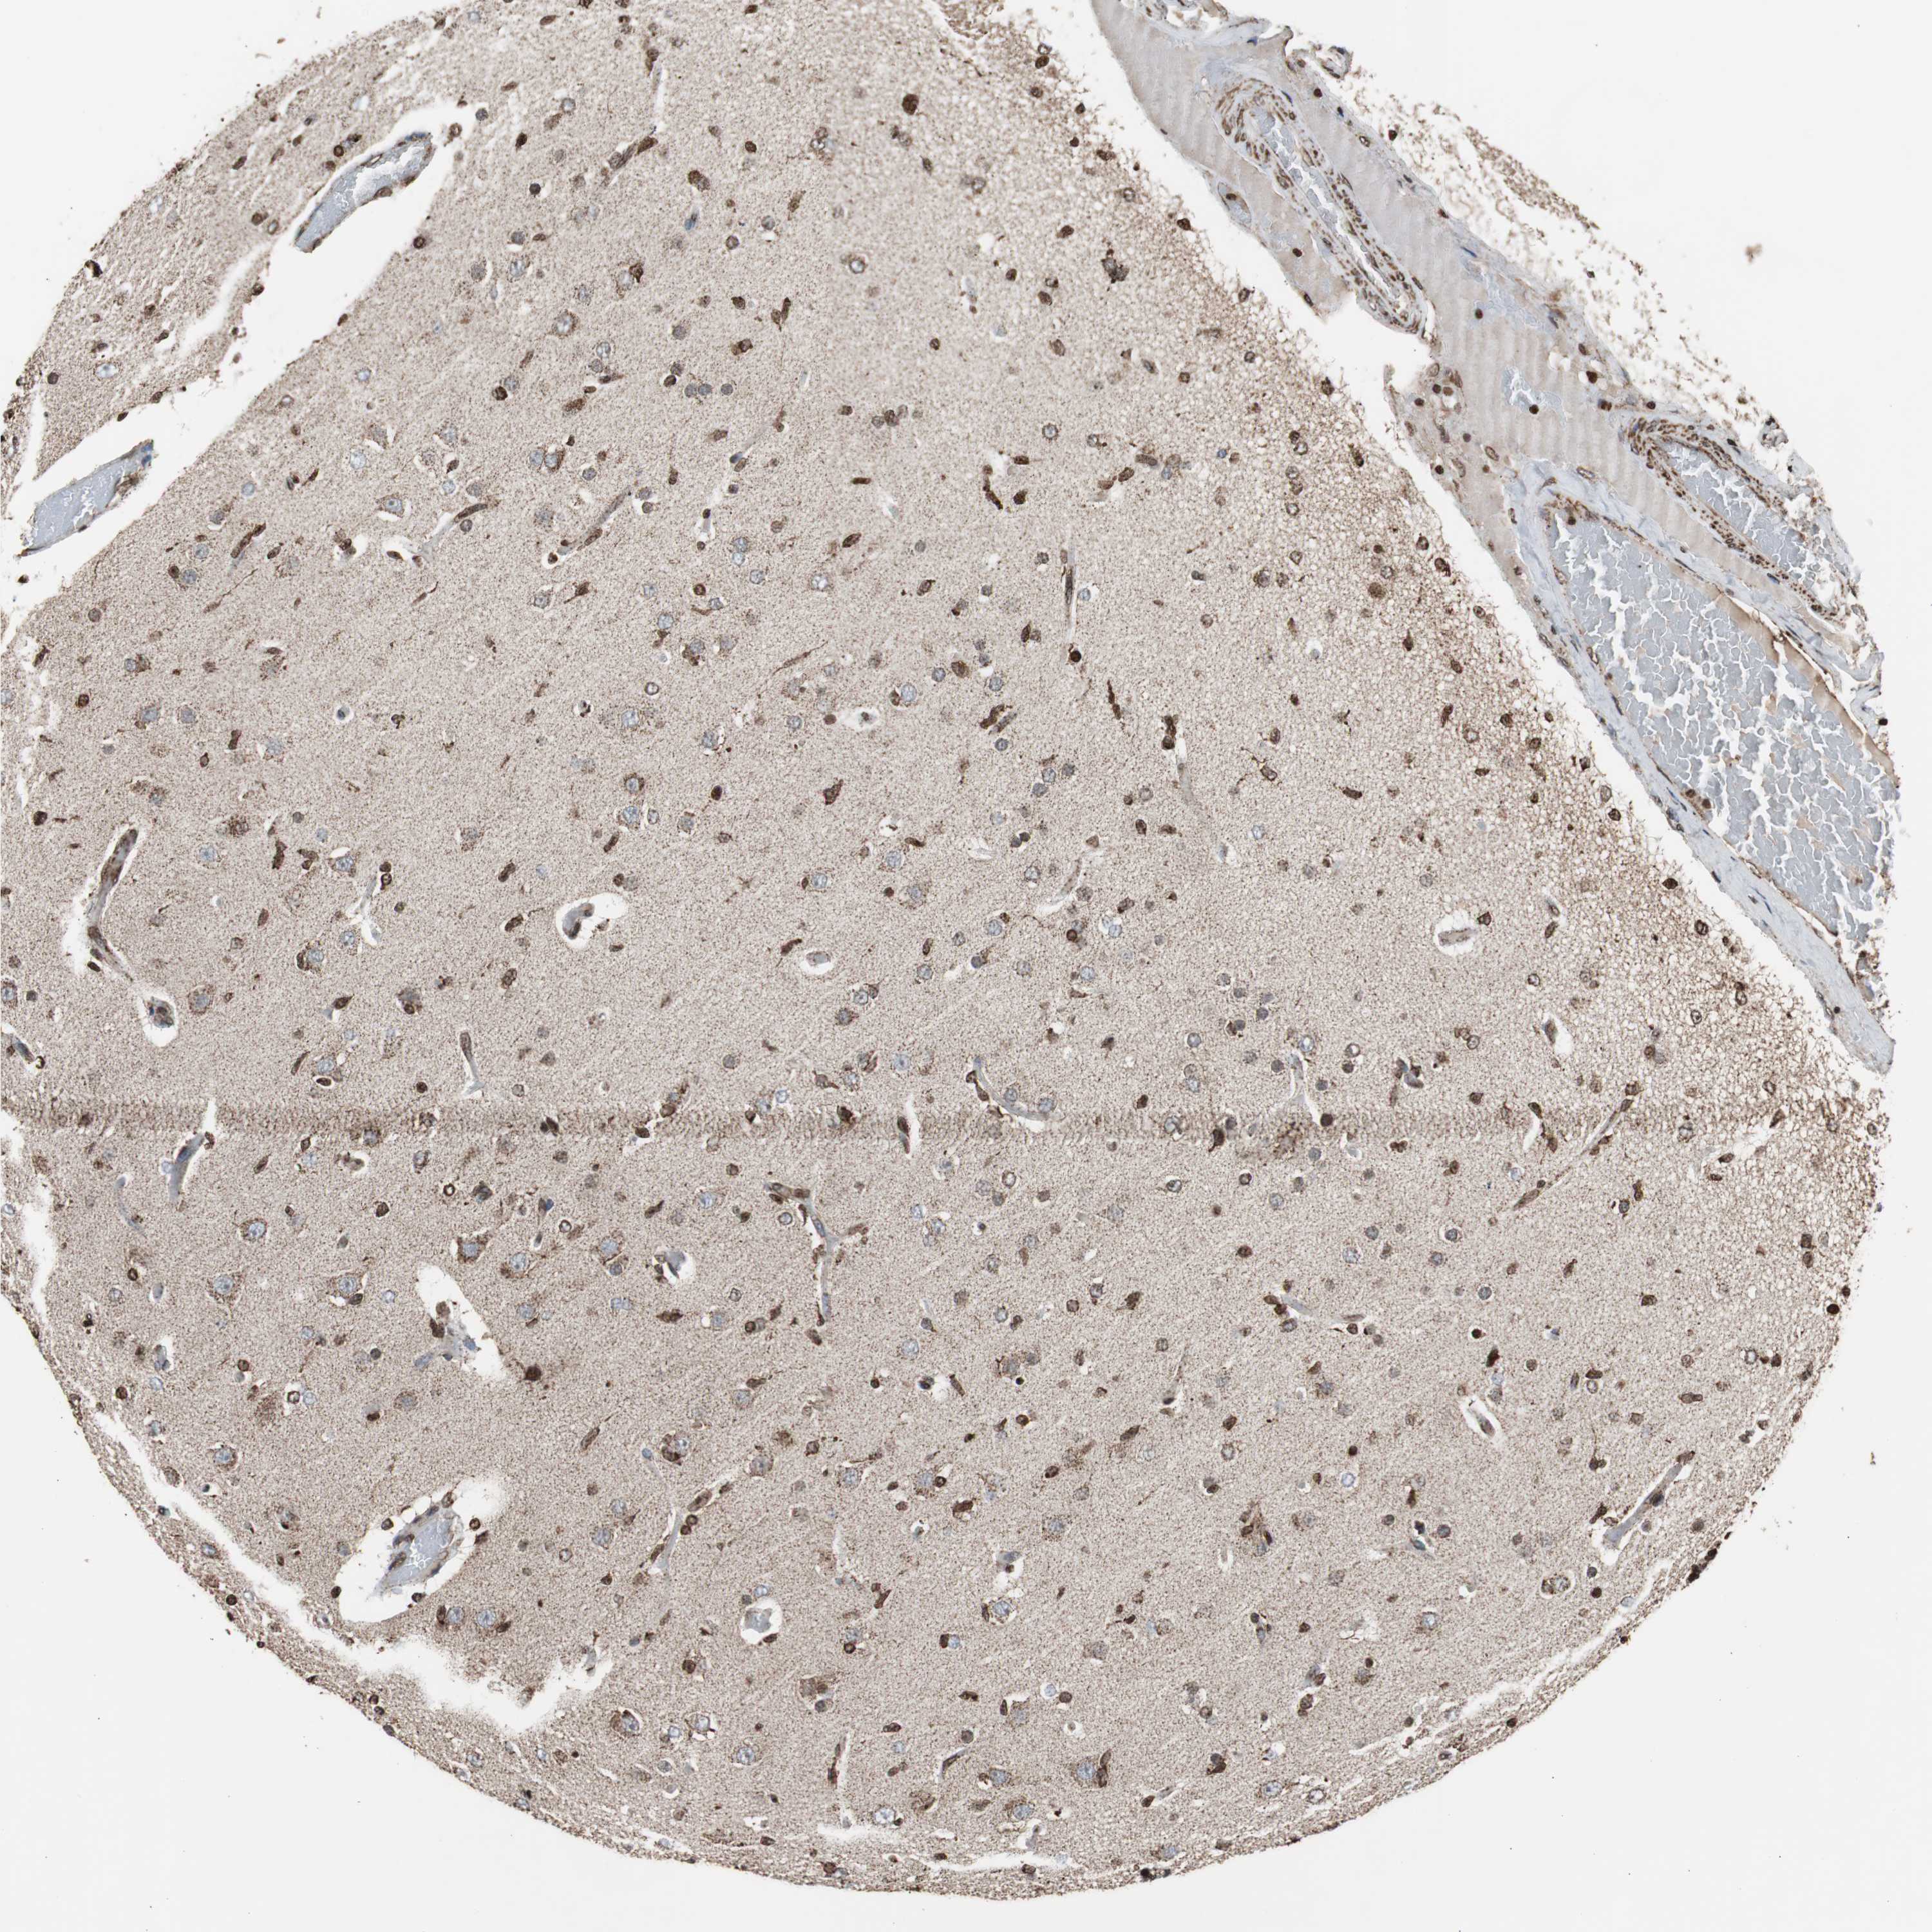

GLIOMA - Protein expressioni

A mouse-over function shows sample information and annotation data. Click on an image to view it in a full screen mode. Samples can be filtered based on level of antibody staining by selecting one or several of the following categories: high, medium, low and not detected. The assay and annotation is described here.

Note that samples used for immunohistochemistry by the Human Protein Atlas do not correspond to samples in the TCGA dataset.

Antibody stainingi

Antibody staining in the annotated cell types in the current human tissue is reported as not detected, low, medium, or high, based on conventional immunohistochemistry profiling in selected tissues. This score is based on the combination of the staining intensity and fraction of stained cells.

Each image is clickable and will lead to virtual microscopy that enables deeper exploration of all samples and also displays staining intensity scores, fraction scores and subcellular localization as well as patient and tissue information for each sample.

Antibody HPA000898

Antibody CAB005219

Staining

High

Medium

Low

Not detected

Intensity

Strong

Moderate

Weak

Negative

Quantity

>75%

75%-25%

<25%

None

Location

Nuclear

Cytoplasmic/membranous

Cytoplasmic/membranous,nuclear

Glioma, malignant, High grade

Glioma, malignant, Low grade